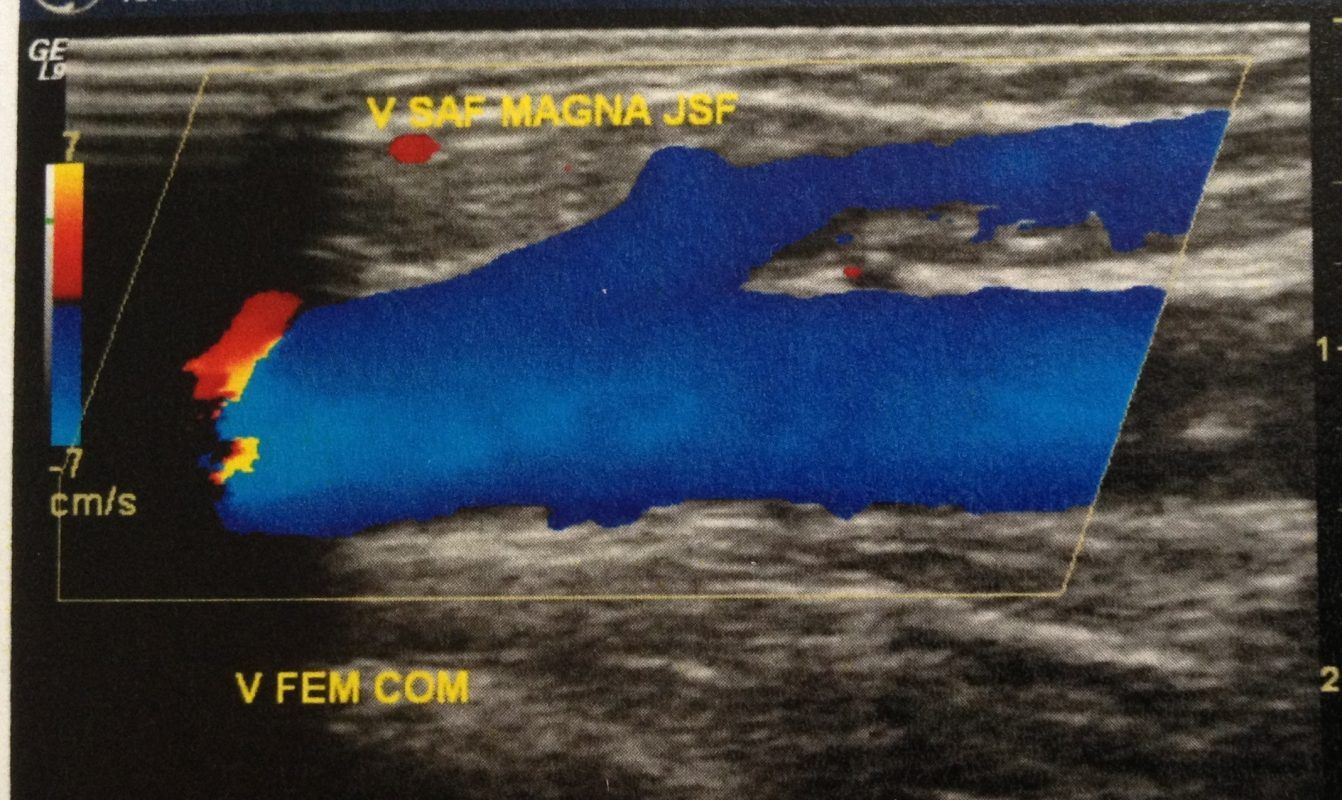

É importante entender que varizes mais calibrosas costumam ser a consequência do mau funcionamento de veias tipo safenas, perfurantes ou do sistema venoso profundo. Por isso o eco Doppler deverá fazer parte essencial dos exames pré operatórios, pois através dos seus achados será possível planejar qual a melhor estratégia cirúrgica utilizar para o caso. Havendo comprometimento de veias safenas ou perfurantes e havendo correlação destas com as varizes apresentadas pela paciente, será fundamental incluir no planejamento cirúrgico o tratamento das veias causadoras das varizes.

Quando houver necessidade de tratamento das safenas ou de veias perfurantes, a técnica de radiofrequência (que utiliza cateter guiado por ultrassom) estará indicada. Com esta técnica o tratamento das safenas e perfurantes doentes é realizado sem cortes (somente punção) e no dia seguinte o paciente costuma retornar às suas atividades normais do dia a dia.